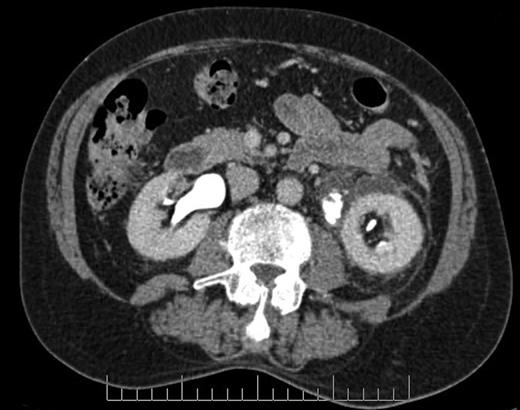

Blood tests revealed a Stage 3 acute kidney injury (baseline renal function was normal) with raised inflammatory markers and elevated PSA compared with baseline (Table 1). A mid-stream urine specimen sent for microscopy, cultures and sensitivities yielded no growth of organisms. A bedside bladder scan revealed a bladder volume of >999 ml, necessitating the insertion of a urethral catheter with a residual volume of 2.4 l, and intravenous antibiotics were commenced. An ultrasound scan (USS) of the urinary tract was performed to evaluate for the presence of hydronephrosis; but while this demonstrated a minor dilatation of the left renal pelvis, it also found a shallow fluid collection around the left kidney extending into the left lateral retroperitoneum, separate from the left psoas muscle (Fig. 1). In the urinary bladder, there was an irregular 4 cm mass on the left posterolateral aspect. In view of the findings, an urgent flexible cystoscopy was performed, revealing a massive median lobe of the prostate protruding up and back into the bladder; the ureteric orifices were not visualized because of this, and the bladder mucosa was normal. The patient subsequently underwent a computed tomography (CT) urogram, which showed bilateral fullness in the pelvicalyceal systems and confirmed a 4.8 × 4.4 × 2.8 cm fluid collection adjacent to the lower pole of the left kidney as detected on the USS, with perinephric stranding. The fluid collection was demonstrated to be extravasated urine on the delayed post-contrast images arising from a defect in the left proximal ureter, and extending down the left paracolic gutter (Figs 2 and 3). The massive prostate was also demonstrable (Fig. 3).

Coronal section CT image demonstrating fluid collection extending down left paracolic gutter. Also visible are massively enlarged prostate and urinary extravasation from left ureter.